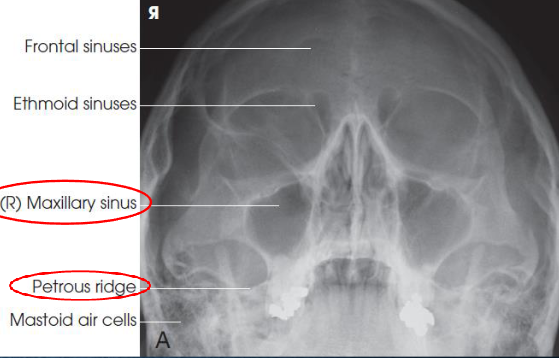

Parietoacanthial (Waters) sinuses

patient position:

upright

MSP centered to midline

part position:

rest chin on vertical grid devie

hyperextend neck to place OML at 37 degree angle from IR

MSP and MML perpendicular to IR

center IR to acanthion

respiration suspended

CR:

horizontal, exits acanthion

collimation:

1 inch beyond the lateral skin shadows, superiorly to include just the shadow of the top of the head, and inferiorly to the occulsal plane

Parietoacanthial (Waters) sinuses image criteria

demonstrates:

maxillary sinuses

petrous pyramids lying inferior to maxillary floor

frontal and ethmoid sinuses are distorted

insufficient extension: petrosa are projected over the inferior portions of the maxillary sinuses

overextension: maxillary sinuses are foreshortened, and antral floors are not shown

OML in proper position:

petrous pyramids lying immediately inferior to floor of maxillary sinsues

symmetric orbits and maxillary sinuses

MSP of head aligned with long axis of collimated field

air-fluid levels, if present